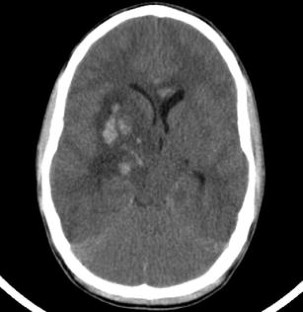

In the management of severe head injuries, the use of intraventricular catheters for intracranial pressure (ICP) monitoring and the option of cerebrospinal fluid drainage is gold standard. In children and adolescents, the insertion of a cannula in a compressed ventricle in case of elevated intracranial pressure is difficult; therefore, a pressure sensor is placed more often intraparenchymal as an alternative option.

In cases of persistent elevated ICP despite maximal brain pressure management, the use of an intraventricular monitoring device with the possibility of cerebrospinal fluid drainage is favourable. We present the method of intracranial catheter placement by means of an electromagnetic navigation technique.